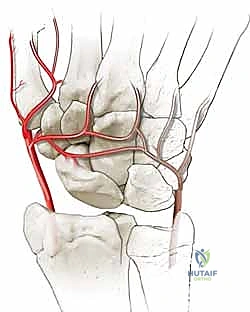

المشكلة الكبرى التي تواجه العظم الزورقي تكمن في التروية الدموية (Blood Supply). الدم يدخل إلى العظم الزورقي من الجزء البعيد (Distal pole) ويتجه نحو الجزء القريب (Proximal pole) في اتجاه عكسي (Retrograde). لذلك، عند حدوث كسر في منتصف العظم، ينقطع الدم عن الجزء القريب، مما يؤدي إلى عدم التئام الكسر (Nonunion) وفي كثير من الأحيان موت العظم (Avascular Necrosis).

متلازمة SNAC (Scaphoid Nonunion Advanced Collapse) هي حالة تدهور تدريجي ومأساوي لمفصل الرسغ. تبدأ القصة بكسر في العظم الزورقي (غالباً بسبب السقوط على يد ممدودة). إذا لم يتم تشخيص هذا الكسر أو لم يلتئم بشكل صحيح، فإن العظم الزورقي ينقسم إلى قطعتين تتحركان بشكل غير طبيعي ومستقل عن بعضهما البعض.

هذه الحركة غير الطبيعية تخلق احتكاكاً مستمراً (Micro-trauma) مع العظام المجاورة، وتحديداً عظم الكعبرة (Radius). بمرور الوقت (أشهر أو سنوات)، يؤدي هذا الاحتكاك إلى تآكل الغضاريف الناعمة التي تغطي العظام، مما يسبب خشونة مفصلية شديدة (Osteoarthritis).

تُعد عملية استئصال القطب البعيد للعظم الزورقي (Excision of the Distal Pole of the Scaphoid) حلاً جراحياً ذكياً ومبتكراً. الفكرة الميكانيكية وراء هذه الجراحة هي: "إذا كان القطب البعيد للعظم الزورقي هو الذي يحتك بعظم الكعبرة ويسبب الألم والخشونة، فلنقم بإزالته مع الحفاظ على باقي هياكل الرسغ".

- الاستئصال الدقيق: باستخدام أدوات جراحية ميكروسكوبية دقيقة، يتم استئصال حوالي 3 إلى 4 مليمترات من القطب البعيد للعظم الزورقي. هذه الكمية كافية لمنع الاحتكاك مع عظم الكعبرة، وفي نفس الوقت تحافظ على استقرار الأربطة.